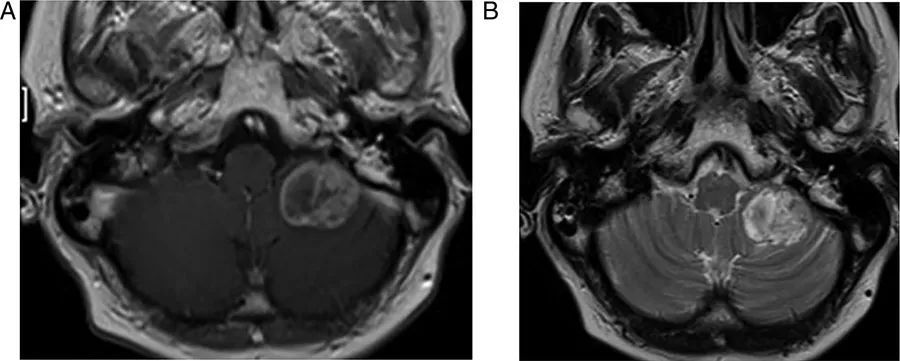

图1  桥小脑角区正常解剖